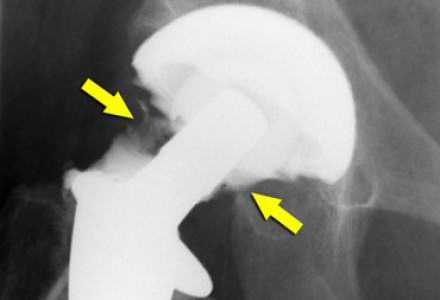

Признаки расшатывания эндопротеза тазобедренного сустава: как определить?

Методика доказала на практике свою эффективность, однако, даже самые совершенные технологии могут в долгой перспективе привести к возникновению осложнений. Нестабильность частей эндопротеза - самая часто встречающаяся патология, которая может вызвать нежелательные последствия и привести к необходимости повторной операции.

К сожалению, современные научные и лабораторные исследования не смогли определить материал для протезов, которые бы не наносил абсолютно никакого вреда здоровью человека. В результате трения компонентов имплантата друг о друга мельчайшие частицы оседают в окружающих тканях, вызывая инфекционные процессы и отмирание тканей. Также может нарушится локальное кровообращение. Поэтому при появлении первых признаков расшатывания эндопротеза тазобедренного сустава следует немедленно обратиться за помощью к лечащему врачу.

Остеолиз

К образованию данного процесса может привести частичное или полное разрушение кости, которое наступает в результате взаимодействия компонентов протеза с живой тканью.

Диагностика нестабильности протеза

При наступлении первых симптомов нестабильности эндопротеза тазобедренного сустава либо до появления таковых не будет лишним пройти курс диагностических мероприятий. Врач назначит следующие виды обследования:

- рентгенологическое исследование тазобедренного сустава;